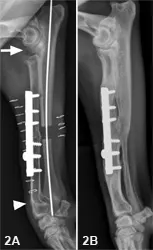

• Lateral views of the left (Figure 1A) and right (Figure 1B) radius/ulna show the left limb with normal, open physes in the distal radius and ulna, as well as the presence of an IV catheter.

• The distal right radial physis is closed (white arrowhead) and large gaps are present (white arrow) between the:

• (1) right humeral condyle and radial head, and

• (2) coronoid process of the ulna and radial head

Figure 1. Lateral views of the left (1A) and right (1B) radius/ulna.